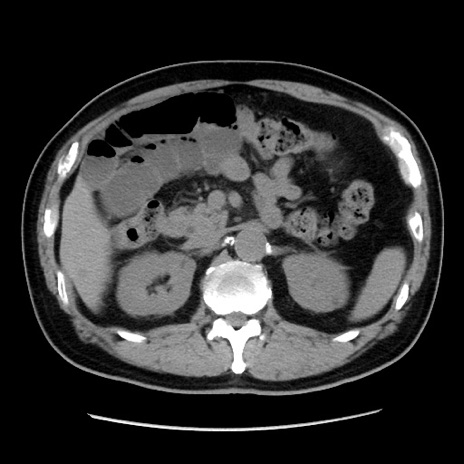

症例16(横断像)

【症例】 70歳代男性

【主訴】 腹痛、嘔吐

【現病歴】 約1ヶ月前より間欠的に腹痛と嘔吐あり、当院消化器内科を受診したところCTで多発する肝臓のLDAを指摘され、精査中であった。以降は消化器症状は安定していたが、2日前より嘔気と腹痛があり、同日より排便・排ガスが消失した。改善認めず、 本日、救急外来を受診した。

【既往歴】 大腸ポリープ切除後。

【身体所見】意識清明・会話良好、BT 36.3℃、BP 127/80mmHg、 P 80bpm、腹部:膨満あり、平坦・軟、上腹部正中および下腹部正中に圧痛あり、反跳痛なし、筋性防御なし。

【データ】WBC 7200、CRP 0.77